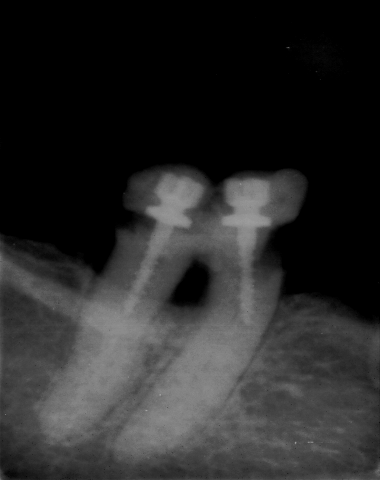

dernier essai je n arrive pas envoyer images

Oui, bon, ta pano est parfaite, ne pese plus que douze kilos.Quand tu es sur:

La voila en PJ

Pano annie1 drczop - Eugenol